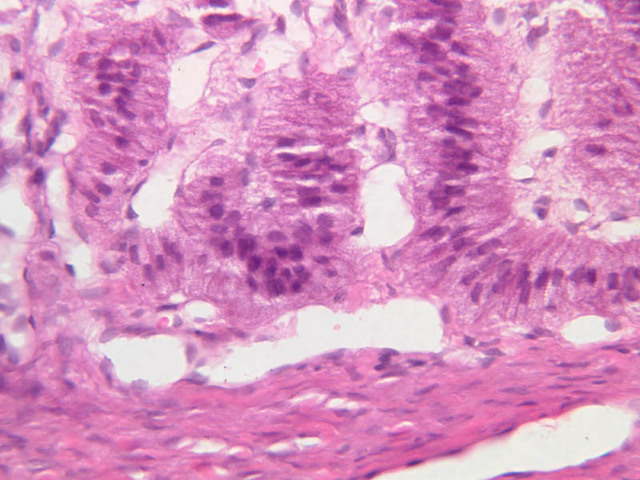

The thyroid gland (slide B-51, lead hematoxylin [10x, 20x, 40x, 40x]; B-52, H&E [10x-labeled, 20x, 40x-labeled, 40x]; B-53, PAS [2.5x, 10x, 20x, 40x]) consists of many closely packed, roughly spherical structures known as follicles, which are enclosed in a thick connective tissue capsule. Connective tissue septa extend from the capsule into the substance of the gland, carrying numerous blood vessels. Follicular cells are arranged as shells of simple cuboidal epithelium surrounding a gelatinous mass known as colloid. Look for a ring of epithelial cells around the homogeneous, pink-staining colloid. The cytoplasm of the follicular cells (principal cells) is faintly basophilic. The follicular cells secrete thyroglobulin, a glycoprotein, which is stored extracellularly in the colloid. In response to TSH, the follicular cells endocytose the colloid and hydrolyze it to form thyroxine. You can see where colloid has been resorbed because this process leaves small holes in the colloid adjacent to the follicular cells. These holes are known as resorption lacunae (B-52 [10x, 20x, 40xlabeled]). Very active follicles may exhibit a columnar epithelium and increased numbers of resorption lacunae. Between follicles, the stroma of the thyroid gland consists of a thin layer of connective tissue and a rich capillary network. Parafollicular cells (light cells or C cells) are located in the connective tissue between follicles or adjacent to follicular cells within follicles. When they lie within the follicular wall, the parafollicular cells do not reach the lumen. Parafollicular cells are slightly larger than the follicular cells and, in H & E preparations, have a more lightly stained cytoplasm (B-52, H&E [10x, 20x, 40x-labeled] [10x-labeled, 20x, 40x-labeled] [10x, 20x, 40x] [10x, 20x, 40x]; B-53, PAS [10x, 20x, 40x]). Parafollicular cells are readily identifiable in slide B-51 (stained with lead hematoxylin), where they appear as purplish-black structures in which the nuclei are difficult to discern (B-51 [10x, 20x, 40x-labeled]). These cells secrete calcitonin, which lowers serum calcium levels by inhibiting bone resorption and accelerating osteoid calcification.